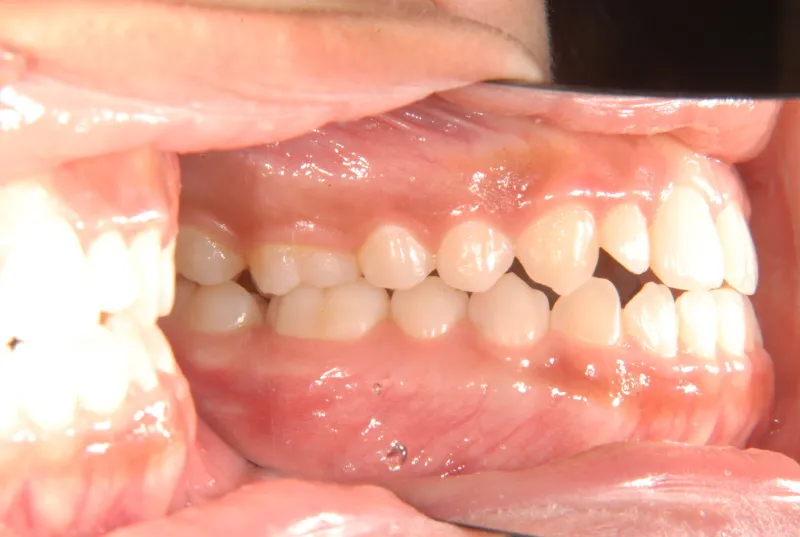

開咬・舌癖・18歳女性

初診時年齢 高校生 (女性) 主訴 開咬 舌癖

状態 前歯で噛めない(開咬/オープンバイト)